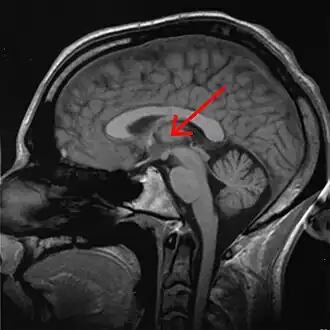

Thalamus

![]() Thalamus marked (MRI cross-section) | |

The thalamus (pl.: thalami; from Greek θάλαμος, "chamber") is a large mass of gray matter on the lateral wall of the third ventricle forming the dorsal part of the diencephalon (a division of the forebrain). Nerve fibers project out of the thalamus to the cerebral cortex in all directions, known as the thalamocortical radiations, allowing hub-like exchanges of information. It has several functions, such as the relaying of sensory and motor signals to the cerebral cortex[1][2] and the regulation of consciousness, sleep, and alertness.[3][4]

Anatomically, the thalami are paramedian symmetrical structures (left and right), within the vertebrate brain, situated between the cerebral cortex and the midbrain. It forms during embryonic development as the main product of the diencephalon, as first recognized by the Swiss embryologist and anatomist Wilhelm His Sr. in 1893.[5]